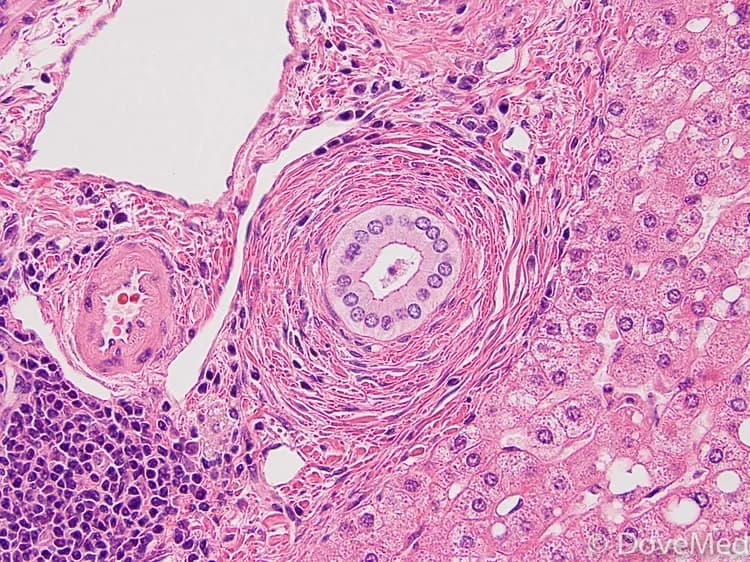

Primary Sclerosing Cholangitis (PSC) is considered to be an autoimmune disease that is characterized by inflammation of the biliary duct (duct that carries bile from the liver to the small intestine) which ultimately results in scarring. Test your knowledge of this disease by taking our quiz!